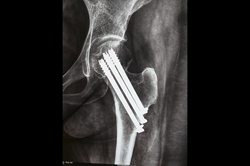

Neck Femur Fracture